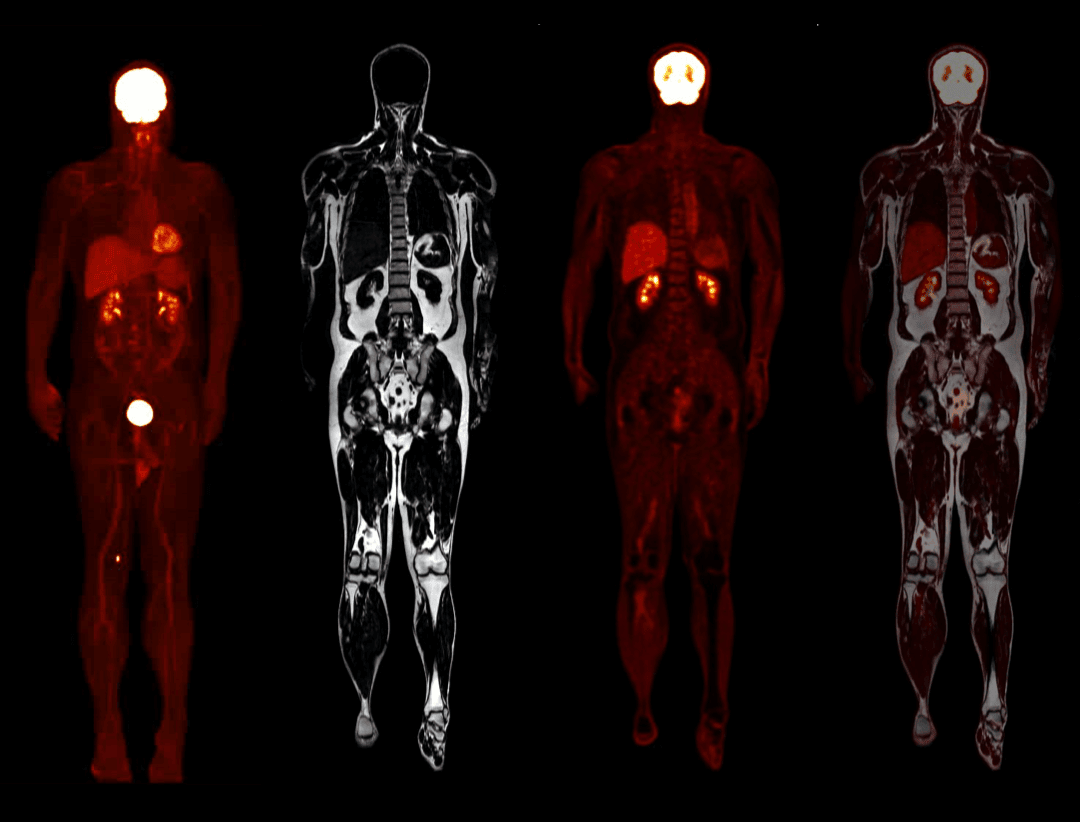

Noua generație de imagistică PET/MRI – acum realizată

uPMR 790 permite imagistică simultană PET/MRI cu rezoluție temporală și spațială ridicată. Această tehnologie redefinește standardele clinice și de cercetare, oferind imagini anatomice și funcționale în timp real.

Imagistică whole-body